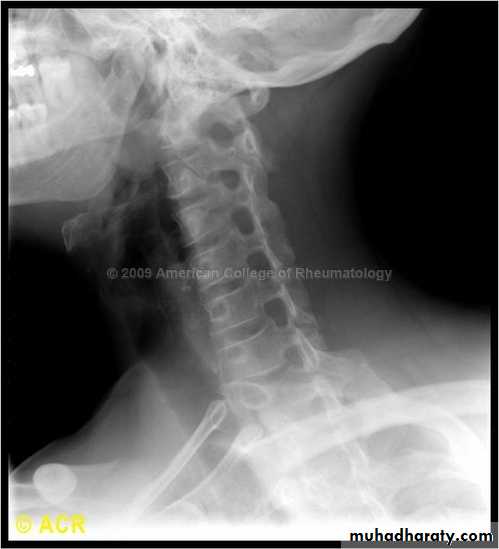

DIAGNOSISX RAY

Anterio posterior X ray radiograph.lateral radiographs with the head in flexion and extension may revealinstability that is not shown in the routine lateral film.

oblique views

at 45° are especially helpful

a special projection

through the open mouth.

Computed tomography (CT)

and magnetic resonance imaging (MRI).